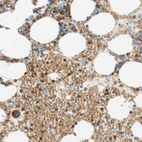

Immunohistochemical staining of human Bone marrow shows moderate membranous and cytoplasmic positivity in erythrocytes and hematopoietic cells.